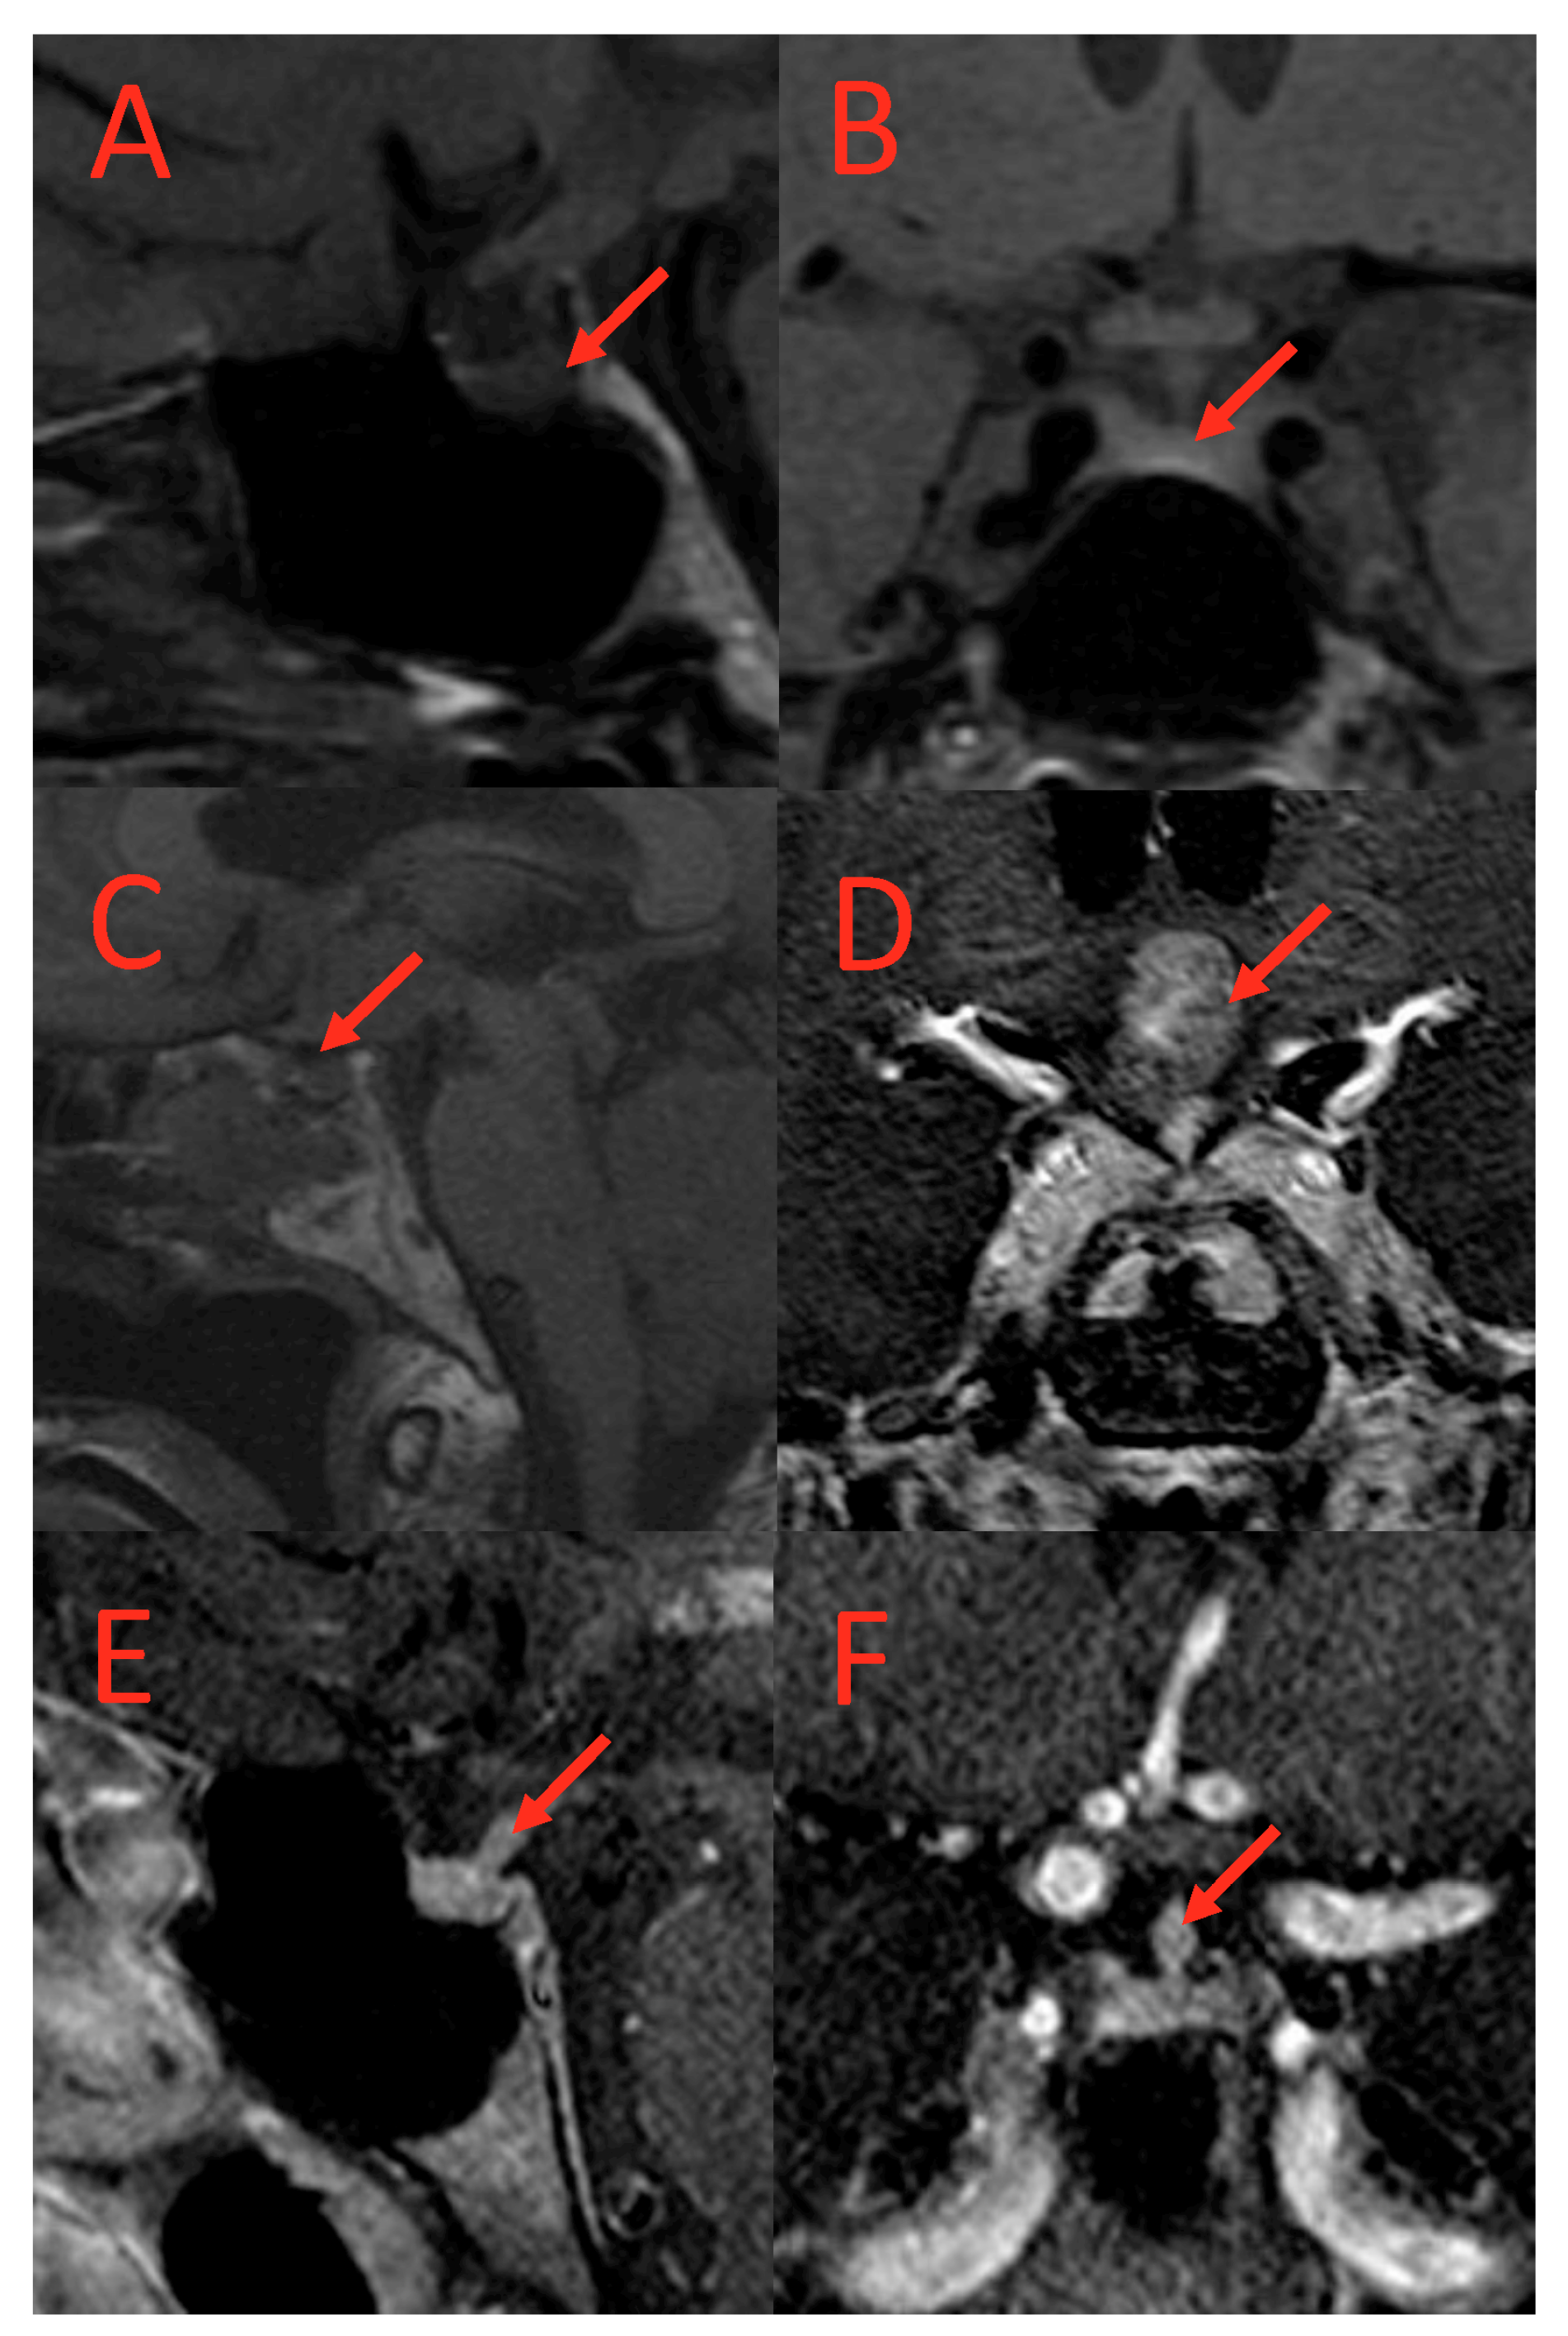

2.3. Radiological Assessment

| Absent Posterior Pituitary Bright Spot, n (%) | 22 (36.07) | 14 (63.64) | 8(20.51) | <0.01 |

| Abnormal Pituitary Imaging, n (%) | 29 (47.54) | 18 (81.82) | 11 (28.21) | <0.01 |

| Absent Pituitary Bright Spot | 12.84 (3.28 to 65.04) | |

| Abnormal Pituitary Imaging | 10.6 (2.84 to 48.29) | |